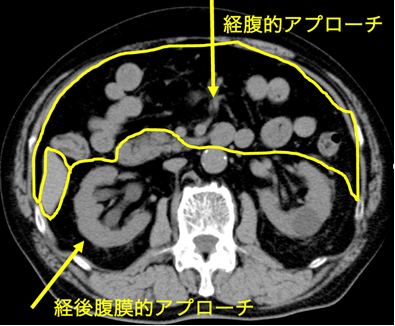

泌尿器科で扱う臓器は副腎、腎、尿管、膀胱、前立腺、尿道、精巣(睾丸)などです。これらの臓器のある場所は「腹膜」という膜構造で仕切られ、胃腸や肝臓などの消化器臓器の背中側「後腹膜腔」に位置します。

副腎や腎に対する手術は、直接背中側から目的の臓器に到達する方法(経後腹膜到達法)、「腹腔」と呼ばれる消化器臓器のある場所を経てそれらを除けながら後ろにある臓器に到達する方法があります(経腹到達法)。